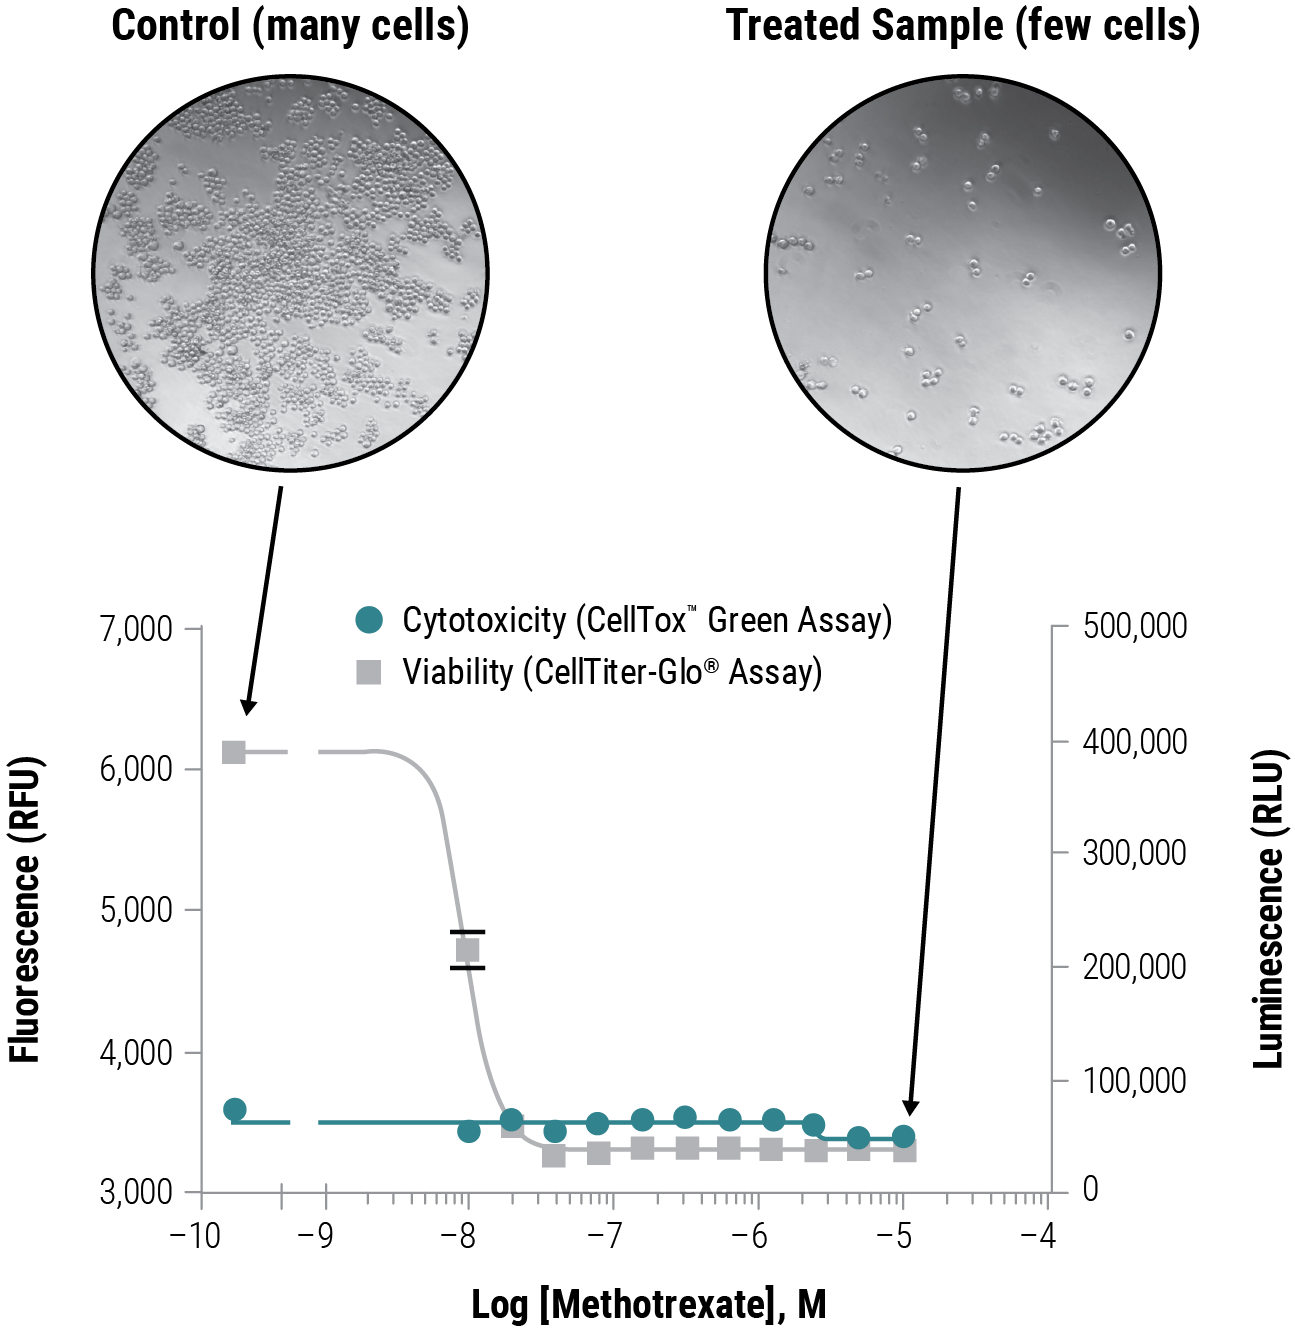

ウェルあたりの情報量を増加させるマルチプレックスアッセイ

細胞毒性と細胞生存性の測定

ここでは、CellTox™ Green DyeをK562細胞と混合し、細胞をプレートに播種した後、化合物を投与しました。72時間の曝露終了時にCellTiter-Glo® Cell Viability Assay試薬を添加し、発光(生存率)を測定しました。これら2つの細胞の健全性に関する逆の指標は、EC50 の一致という結果を示しました。